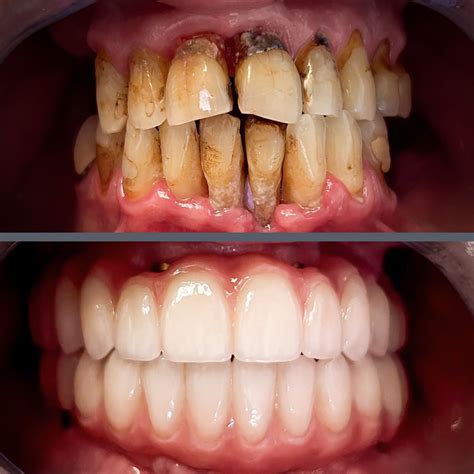

The journey toward oral health is often overlooked until significant symptoms arise, and advanced periodontal disease, also known as advanced periodontitis, represents the most severe stage of gum infection. At this critical juncture, the infection has progressed far beyond the surface of the gums, causing deep-seated damage to the tissues and the underlying bone that supports your teeth. Recognizing the warning signs early is crucial, but understanding the complexities of this advanced stage is essential for seeking the right treatment to prevent permanent tooth loss and systemic health complications.

Advanced periodontal disease occurs when the bacteria in your mouth—which have already caused initial gingivitis and progressed into moderate periodontitis—begin to destroy the fibers and bone that anchor your teeth in place. As the infection deepens, the gums pull away from the teeth, creating "pockets" that become infected and difficult to clean. Over time, the body’s own inflammatory response to this infection begins to break down the surrounding bone and periodontal ligament, leading to loose teeth, shifting, and, eventually, tooth loss.

Once diagnosed, the primary goals of treatment are to stop the progression of the disease, eliminate existing infection, and rebuild the supporting structures where possible. Because the damage is extensive, professional treatment is necessary.

When the disease is advanced, surgical procedures are often the most effective way to restore health.